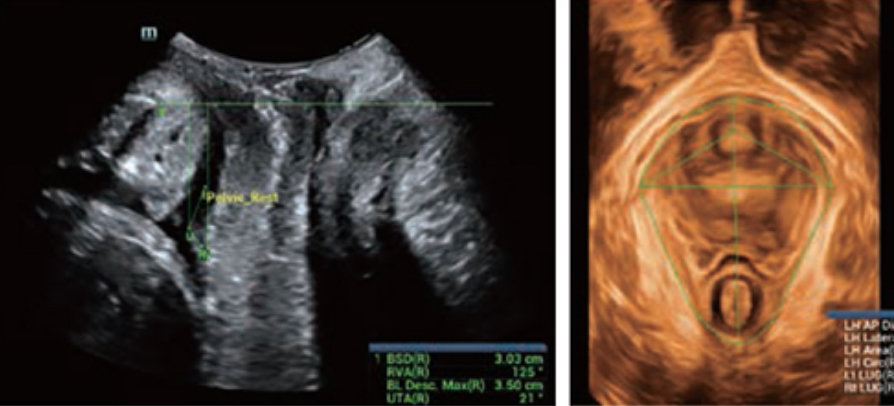

Realizing the increasing importance of ultrasound diagnosis on pelvic floor disorders, the new Resona 6 with Zone Intelligence provides a new solution to greatly simplify the operation procedures, and to minimize the exam time for a standardized evaluation on pelvic floor. With extremely simple user-interaction, it generates a standard coordinate system and automatically provides all related measurements within a few seconds.